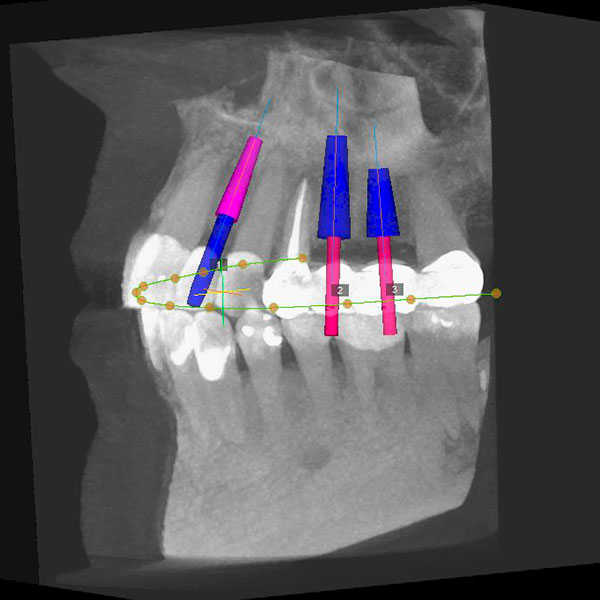

A virtual surgery can be done on a computer to plan exactly what size, position, depth, and angulation your implant should be, which helps determine if you require or would benefit from any bone or gum grafting before or during implant placement.

The Blairsville Dentistry team is always planning for your safety and comfort, which comes in many forms during the implant process. The 3-D planning process using CT scans is absolutely critical to this goal. You are a three-dimensional human 🙂 , and any implant surgery should be planned in a 3-D manner to safely avoid important anatomical structures like your sinuses and nerves.

3. 3D guided Surgery

Once we’ve developed a personalized treatment plan for you and decided on the positioning of the implants, we use surgical guides on as many procedures as possible to help ensure that every implant is placed exactly how we want it. These guides are made from the CT scans and are 3-D printed to have a very high accuracy for safety and predictability every time.

Guides can be used for a variety of procedures, ranging from implant placement, to bone reduction, to proper positioning of restorative components such as “screw-in” or “hybrid” dentures.